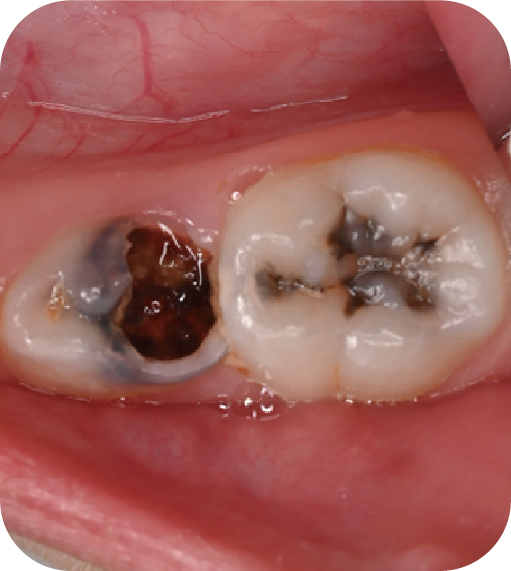

后磨牙,也就是大牙咬合面上凹凸不平的裂隙,這就是“窩溝”。窩溝有很多形狀,有的是狹長的裂隙形狀,還有的在牙齒深處又會分成幾條小溝。這些地方用牙刷很難深入清潔,于是就成了衛(wèi)生死角,細菌特別喜歡在里面生存,不斷產(chǎn)酸腐蝕牙齒,蛀牙就這樣產(chǎn)生了。如果我們用窩溝封閉把這些衛(wèi)生死角封起來,那既可以杜絕食物和細菌進入窩溝內(nèi),也可以讓窩溝處的清潔變得更簡單,這就是做窩溝封閉的目的。同時它也是世界衛(wèi)生組織、國家衛(wèi)健委都推薦的防齲方法。